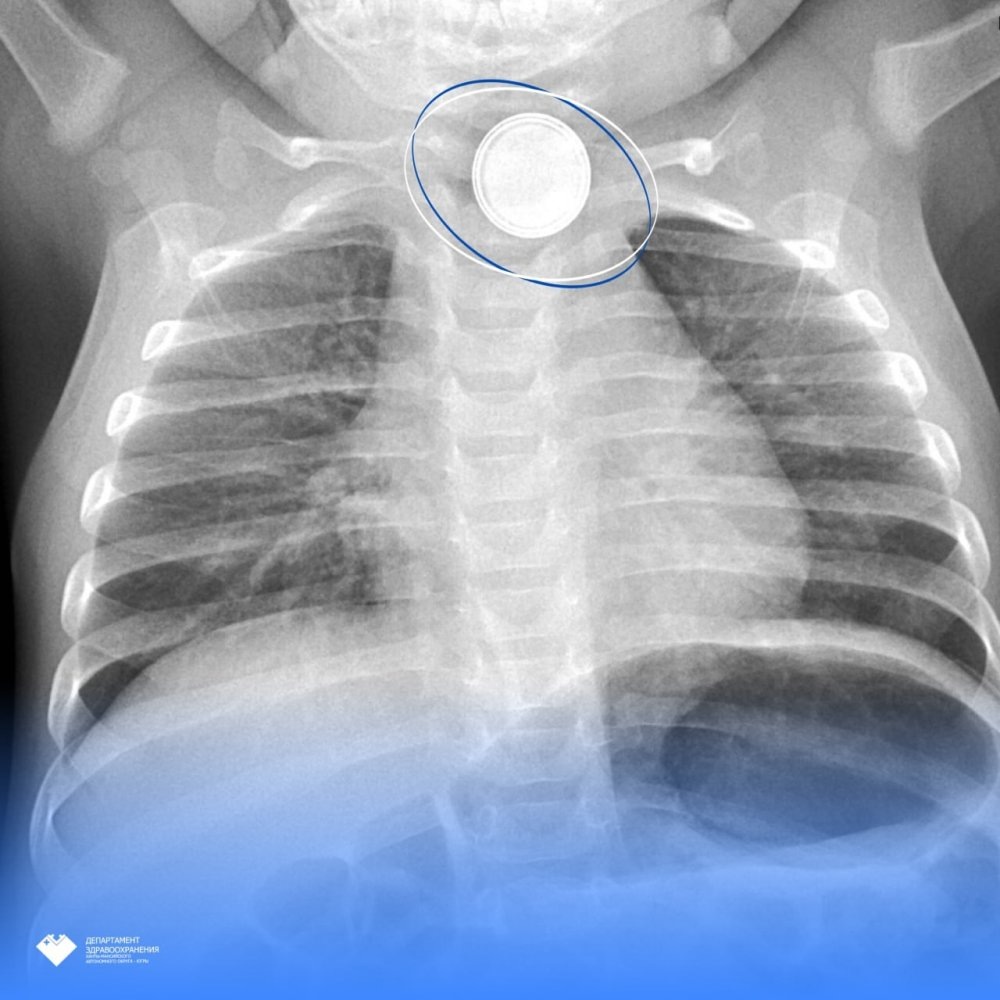

В Сургуте медики успешно провели сложную операцию 11-месячному ребенку, проглотившему круглую батарейку. Родители сразу вызвали скорую, когда заметили опасную ситуацию. Об этом говорится в телеграм-канале департамента здравоохранения Югры.

Сначала малыша доставили в Нефтеюганскую больницу, где рентген показал инородный предмет в пищеводе. Ребенка экстренно перевезли в Центр охраны материнства и детства Сургута. Обследование выявило серьезный ожог пищевода от батарейки диаметром 1,5 см.

Опытная команда врачей провела срочную операцию. Хирург Эльнур Джафаров вместе с коллегами удалил опасный предмет. Через месяц обследование показало, что пищевод восстановился, и малыш чувствует себя хорошо. Сейчас он дома, но за ним по-прежнему наблюдают.